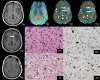

We evaluate the value of MR diffusion tensor imaging (DTI) and dynamic susceptibility-weighted contrast material-enhanced perfusion-weighted imaging (PWI) in preoperative grading of supratentorial nonenhancing gliomas. This institutional review board-approved, Health Insurance Portability and Accountability Act-compliant retrospective study involved 52 patients: 37 with low-grade gliomas (LGGs) and 15 with high-grade gliomas (HGGs). The mean trace apparent diffusion coefficient (ADC), minimal ADC, mean fractional anisotropy (FA), maximal FA, and maximal relative cerebral blood volume (rCBV) ratio of the lesions were measured and compared between LGG and HGG. The efficacy of the above parameters in grading supratentorial nonenhancing gliomas was evaluated. There was no significant difference in rCBV ratio, minimal ADC, and mean ADC between LGG and HGG (p > 0.05). The mean and maximal FA values of LGG were significantly lower than the values of HGG (p < 0.001). The receiver operating characteristic analysis showed that the mean FA with a cutoff value of 0.129 and the maximal FA with a cutoff value of 0.219 could differentiate between LGG and HGG with specificity of 69.2% and 76.9%, respectively, and sensitivity of 93.3% and 100.0%, respectively. The combination of mean FA and maximal FA based on the linear discriminant analysis improved the diagnostic accuracy with specificity of 92.3% and sensitivity of 86.7%. These findings were better than maximal rCBV ratio, mean ADC, and minimum ADC. The mean FA and maximal FA, used individually or combined, may be useful in preoperative grading of supratentorial nonenhancing gliomas.